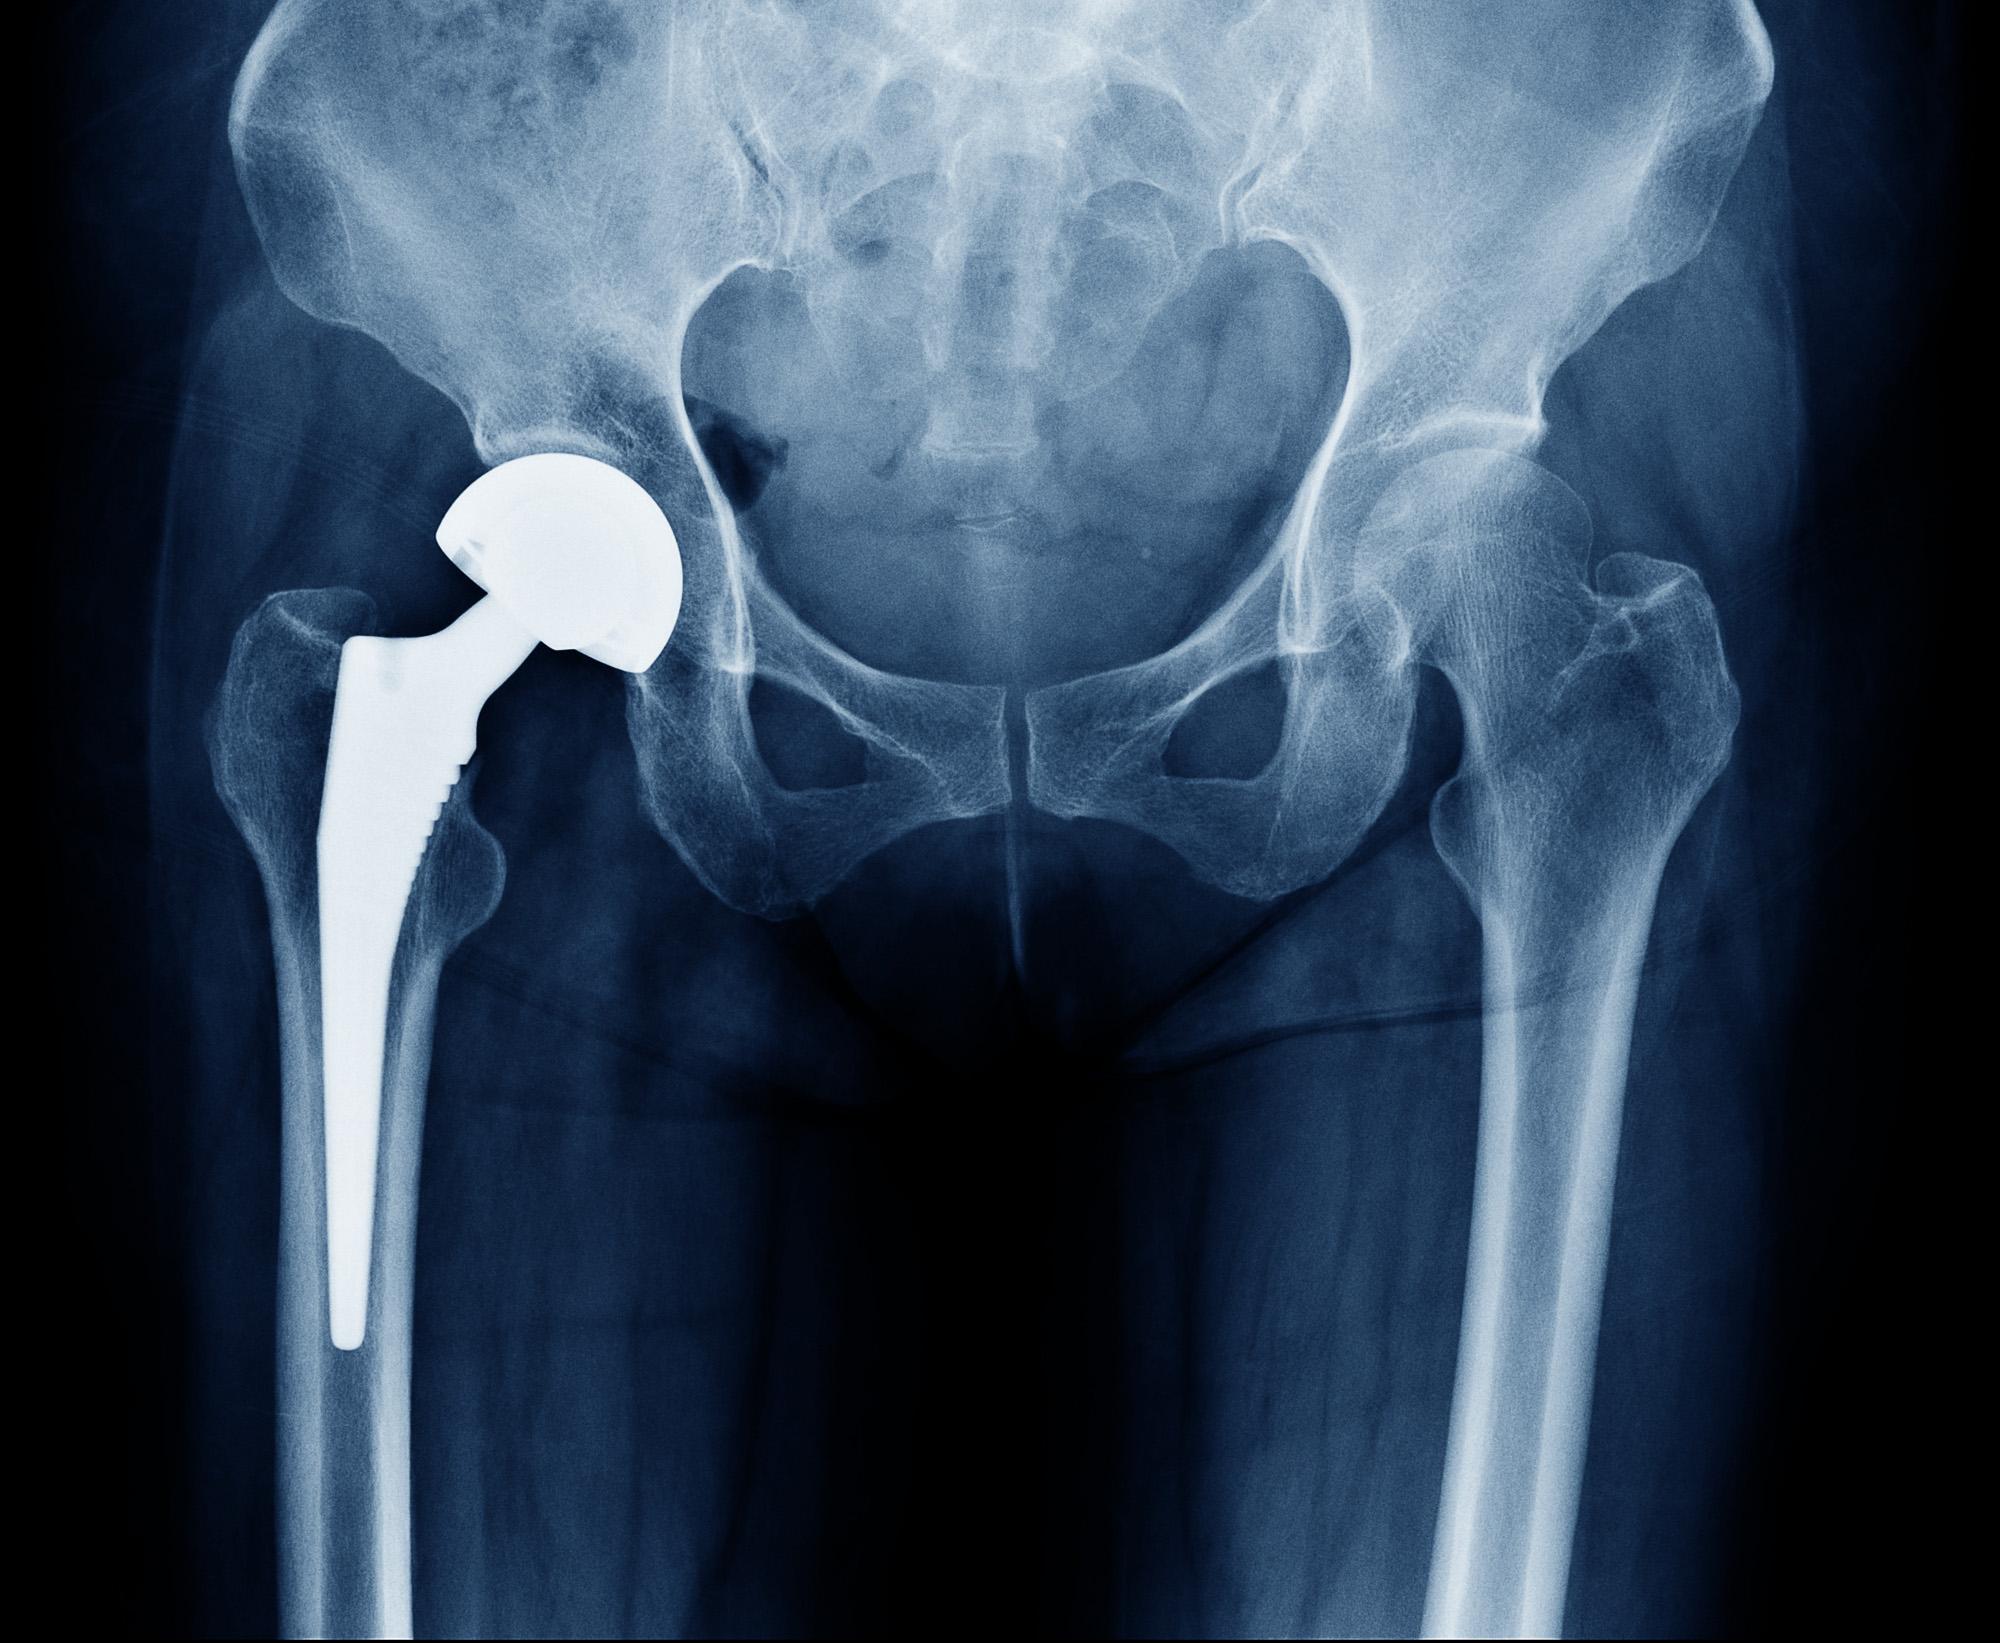

What Is Hip Joint Replacement

What Is Hip Joint Replacement

Total Hip Replacement OrthoSport Victoria

Total Hip Replacement BJISG

Total Hip Replacement Hip Osteoarthritis